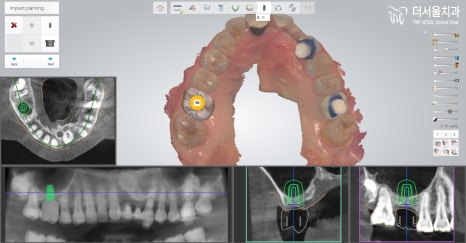

그렇기에 판교 치과 에서는

해당 방법을 시행하는데 있어

컴퓨터 분석 방법을 이용했습니다.

컴퓨터 분석을 이용하여 확인한 결과,

뼈이식을 어떻게 하면 좋은지

계획을 꼼꼼히 수립 후,

그에 걸맞게 시행했습니다.

우선 이미 빠져있는 # 26에

뼈를 옮겨 심었으며,

픽스처와 지대주, 크라운 세팅으로

먼저 수술을 끝마쳤습니다.